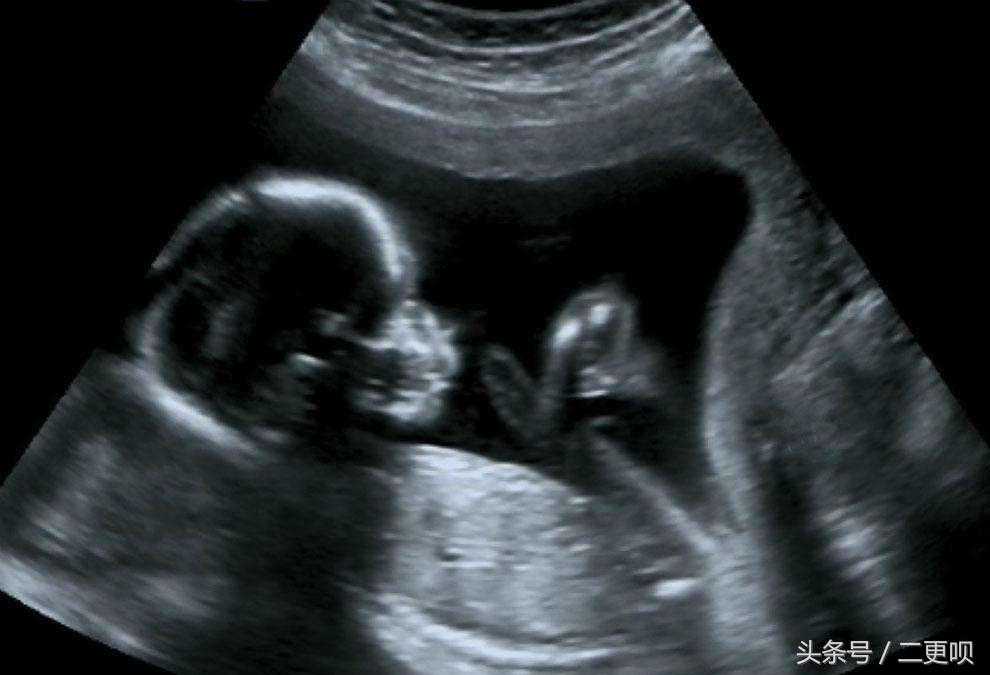

今儿个突然想起昨天表姐去照四维,然后就问她结果如何,表姐说,都挺好的,医生说宝宝发育得很好,但是有个疑问。为何四维图最下面有一段话,着实让表姐想不通。

“相信细心的孕妈都会发现在照四维的时候,医生也会明确表明,超生只检查报告中描述的内容,没有描述的胎儿结构不在检查的范围内”。原来医生明说拉,20-28周做的四维彩超就只能检查出,胎儿鼻唇部、心脏,可发现大部分解剖异常和出生缺陷,如无脑儿、脑积水、脊柱裂、肢体畸形、严重唇腭裂、先天性心脏病等。

几乎所有胎变化儿的内脏器官,在出生前都会持续不断的成长变化,因此并非在早期检查时,为正常状况的器官,就能保证在出生后也一定正常哦。也因为超音波受限于妈妈肚子皮及子宫的阻挡,无法调整胎儿的姿势及位置,无法获得某些角度的影像。为胎儿的成长状况而造成的超音波检查有所限制的情况: